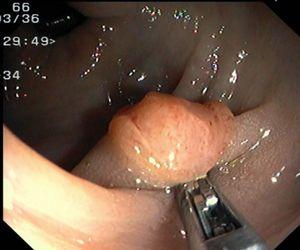

Fig. 4. Examples of protruding lesions with conventional examination and after the application of indigo carmine 0.2-0.5%. a, b) Sessile polyp. c, d) Subpedunculated polyp. e, f) Pedunculated polyp. g, h) Submucosal lesion (indigo carmine shows distinct innominate grooves, ruling out an epithelial lesion). i) Subpedunculated polyp. j) After indigo carmine application, a flat elevated lesion similar in size to the protruding segment is clarified.